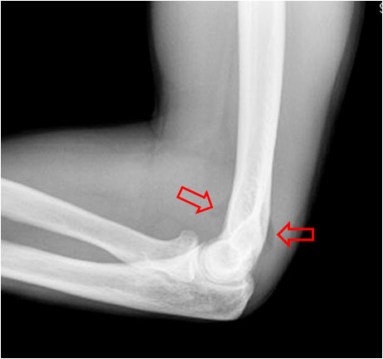

SIGNO DE LA ALMOHADILLA DEL CODO

En condiciones normales, existe una pequeña cantidad de grasa en la cápsula articular del codo, por fuera de la sinovial. En las radiografía laterales esta grasa no es visible ya que queda escondida en la concavidad del olécranon y en la fosa coronoidea.

Sin embargo, cuando se produce un derrame articular, traumático o no, se distiende la sinovial y se desplaza la grasa, produciendo unas radiolucencias triangulares anterior y posterior al extremo distal del húmero (flechas).